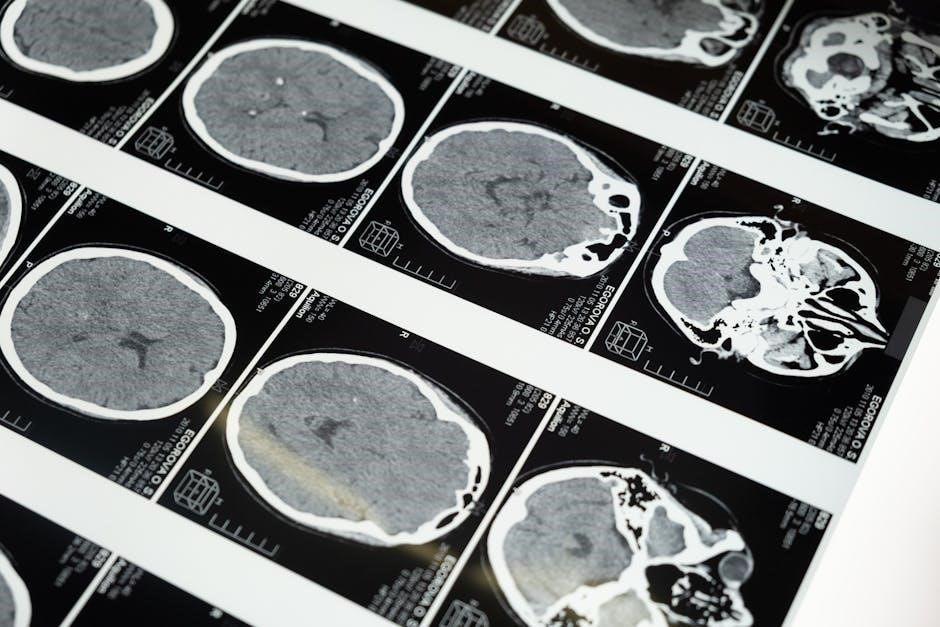

The cerebrum, the brain’s largest component, stands as the command center for higher-level cognitive functions. Divided into two distinct hemispheres – left and right – it orchestrates everything from thought and language to memory and voluntary movement. Each hemisphere isn’t a monolithic entity; rather, it’s partitioned into four primary lobes: the frontal, parietal, temporal, and occipital lobes.

The cerebrum’s architecture is defined by its four distinct lobes, each dedicated to specific cognitive and sensory processes. The frontal lobe governs executive functions, personality, and voluntary movement. Behind it, the parietal lobe integrates crucial sensory information, including touch, temperature, and spatial awareness.

Further back, the temporal lobe is pivotal for auditory perception, language comprehension, and the formation of long-term memories. Finally, the occipital lobe resides at the rear of the brain, solely dedicated to processing visual information – colors, shapes, and depth perception. These lobes don’t operate in isolation; rather, they collaborate seamlessly to create a unified experience of the world.